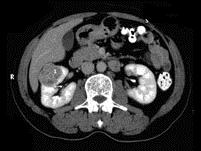

问题 男,56岁,无痛性全程血尿1个月,CT平扫及增强检查如图,下列说法正确的是 ( )

选项 A、右肾静脉及下腔静脉内未见充盈缺损影 B、考虑为右肾上极的肾癌 C、增强扫描皮质期,病灶强化明显,但仍低于肾皮质的强化 D、增强扫描实质期,该灶强化迅速减退,可清楚的分辨其轮廓 E、在右肾上极,肾脏局部隆起,平扫时其密度与肾相近,不易分辨其轮廓